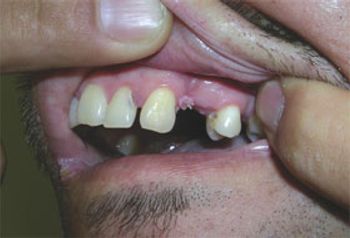

Heart disease, stroke, and cancer are leading causes of death in men, but they present to primary care with a variety of other, often difficult-to-diagnose concerns. Take this week’s photo quiz to test your knowledge of men’s health issues.